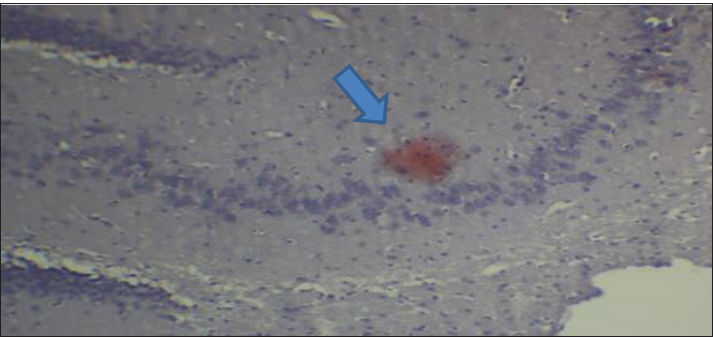

Fig. 2. Effect of gemcitabine, gemcitabine + ALC (25 mg/kg/bw), and gemcitabine + ALC (300 mg/kg/bw) on serum AChE. Histological resultsAccording to the histological investigation, the central nervous system did not contain any beta clusters. The experimental beta-amyloid turns red because it is stained using the pigment Congo red, indicating that the central nervous system is secure from beta-amyloid buildup in the absence of treatment (Fig. 3). The gemcitabine group showed an increase in beta-amyloid accumulation in the rat’s brain, which is stained in red color as shown in Figure 4. However, compared to the gemcitabine group, rats administered gemcitabine plus ALC (25 mg/kg/bw) showed a significant reduction in the buildup of beta-amyloid in the rat’s brain, as depicted in Figure 5. Furthermore, as illustrated in Figure 6, rats treated with gemcitabine + ALC (300 mg/kg/bw) exhibit a significant reduction in the buildup of beta-amyloid in their brains when compared to rats treated with gemcitabine + ALC (25 mg/kg/bw).

Fig. 3. Photomicrograph of the control group’s brain section showing the normal histological architecture without the accumulation of beta-amyloid (congo red, 4×).

Fig. 4. Photomicrograph of the brain section of the gemcitabine group showing the accumulation of beta-amyloid plaques (congo red) (A 4×, B 10×).

Fig. 6. Photomicrograph of the brain section of the Gemcitabine + ALC (300 mg/kg/bw) group showed the accumulation of beta plaques (red) (4×). DiscussionGemcitabine increases the production of ROS, including superoxide radicals, which can lead to oxidative stress. The build-up of these reactive species may contribute to cellular toxicity by increasing protein oxidation, reducing enzyme activity, and compromising cell membrane integrity through lipid peroxidation. Moreover, oxidative stress may facilitate the production of secondary reactive chemicals that worsen cellular damage. Although these mechanisms offer a reasonable explanation for the toxicity caused by gemcitabine, care should be taken when interpreting them because the precise molecular pathways may differ based on the kind of tissue and the settings of the experiment. This investigation found that the fatty acid aldehydes, such as the substance and 4-hydroxynonenal, this investigation found indicating that the Gemcitabine-treated group had significantly greater variations in the bloodstream beta-amyloid levels than the remainder of the participants (Metselaar et al., 2024). The effects of gemcitabine are exclusive to the S-shaped cellular lifecycle. Significant chromosome damage causes chromosomal abnormalities. This drug thus inhibits the capacity of cells with quick division that need replication of DNA to repair individuals, potentially leading to the death of certain nerve cells (Morgillo and Marovino, 2021). Beta-amyloid may have increased in individuals who just received a combination of dying nerve cells generate a lot of amyloids in a type of beta-amyloid (Yin et al., 2021; Goel et al., 2022). ALC, and these assists in minimizing the damaging effects of oxidative stress with tissue and additionally assists in eliminating the chemical toxicology associated with gemcitabine, triggered an important decrease within the concentration of the protein beta-a within animals the fact that switched the package. Nevertheless, it has been found that a concentration of 300 mg/kg/bw was more effective in terms of effectiveness and efficiency compared with the 50 mg/kg/bw dose (Madkour et al., 2022; Wang et al., 2024). Brain beta-amyloid peptide (Abeta) may affect ache stages because ache concentrations are elevated in the vicinity of beta-amyloid plaque. Such data piqued our curiosity about the potential for the enzyme AchE as well as amyloidosis level to fluctuate within tandem, meaning that if beta-amyloid plaques rise, which is this will affect ache, which might ultimately result in cerebral suppression (Mahdi et al., 2021; Bansal et al., 2025). Histological evaluation demonstrated that the group receiving treatment had less beta-amyloid buildup and smaller beta-amyloid deposits compared to this drug category. Amyloid beta precursor amino acids are present in a variety of cellular membrane types and discharge. Amyloids quickly enter the plasma and cerebrospinal fluid. Deposits are lumps of strands and are aggregated from internalized β-amyloids, which pile on over each other as well as compress forming β-pleated or β-folded shapes (Gottwald and Röcken, 2021; Whitfield et al., 2023). Congo red pigment is frequently used to examine amyloidosis because it binds to amyloid fibrils in several components. Additionally, this appears red due to bonds (Antimonova et al., 2024). There was a notable increase in beta-amyloid levels in the Gemcitabine category resulting from the fact that Gemcitabine increases cellular stress from oxidative damage, which in turn causes an increase in beta-amyloid synthesis (Tamagno et al., 2021). Additionally, because ALC is administered, the nervous system produces less beta-amyloid due to lowering the quantity of ROS within the central nervous system, which aids their brain resulting in less beta-amyloid and, consequently, the elimination of the fluorescent red color from the tissues, as changes depicted in figures (Morid et al., 2023; Mateus et al., 2023). ConclusionAccording to the research findings, ALC reduces the negative effects of gemcitabine by primarily lowering the body’s concentrations of beta-amyloid and the buildup of the protein beta-lesions. AcknowledgmentThe authors thank the laboratory staff and colleagues for their technical support and valuable assistance throughout this study. The authors also thank the ethics committee for approving the research protocol and the institution for providing the necessary facilities. Conflict of interestThe authors declare that there is no conflict of interest. FundingNone. Authors’ contributionsMarwa Sabah Majed: Materials and Methods. Fatema Ali Al Kafhage: Results. Hiba Alameri: Discussion. Amaal Sahib Al-Zughaibi contributed to the statistical analysis of the study data. Amna Mohammed Hamza contributed to the writing and preparation of the manuscript. Roaa Noori Ali was responsible for conducting the experimental work and collecting the samples. All authors read and approved the final manuscript. Data availabilityAll data were presented in the study. ReferencesAntimonova, O.I., Polyakov, D.S., Grudinina, N.A., Masterova, K.V. and Shavlovsky, M.M. 2024. Antibodies to Congo red dye as a promising tool for detection and destruction of amyloid. Cell. Tissue. Biol. 18(6), 721–727. Ashraf, G.M. 2023. Neurochemical systems and signaling: from molecules to networks. Boca Raton, FL: CRC Press. Bansal , S., Yadav, M., Bisht, P., Bansal, D., Tushir, S. and Rathore, D. 2025. Β-Amyloid pathways in Alzheimer's disease: mechanisms and therapeutic targets. CNS Neurol. Disord-Drug. Targets. Davidová, M., Sharma, S., McMeel, D. and Loizides, F. 2022. Co-De| GT: The gamification and tokenisation of more-than-human qualities and values. Sustainability 14(7), 3787. Goel, P., Chakrabarti, S., Goel, K., Bhutani, K., Chopra, T. and Bali, S. 2022. Neuronal cell death mechanisms in Alzheimer’s disease: an insight. Front. Mol. Neurosci. 15, 937133. Gottwald, J. and Röcken, C. 2021. The amyloid proteome: a systematic review and proposal of a protein classification system. Crit. Rev. Biochem. Mol. Biol. 56(5), 526–542. Guliyeva, A., Abbasova, M. and Gadzhiev, A. 2025. Blood leukocyte formula in rats exposed to electromagnetic radiation during prenatal development. Adv. Biol. Earth. Sci. 10(3), 511–518; doi:10.62476/abes.103511 Huseynova, L. (2025). Pyruvate kinase modulation in the brain under stress factors: structural, developmental, and molecular perspectives. Adv. Biol. Earth Sci. 10(3), 488–498; doi:10.62476/abes.103488 Javan, M., Ebrahimi, M., Madatli, A., Madatli, F. and Karimova, R. (2025). Acetylation and sirtuins: molecular mechanisms driving metabolic flexibility. Adv. Biol. Earth Sci. 10(3), 547–584; doi:10.62476/abes.103547 Kıran, T.R., Otlu, O. and Karabulut, A.B. 2023. Oxidative stress and antioxidants in health and disease. J. Lab. Med. 47(1), 1–11. Lakshmanan, M. 2021. Cholinoceptor agonists and anticholinesterase agents. In Introduction to basics of pharmacology and toxicology: volume 2: essentials of systemic pharmacology: from principles to practice. Singapore: Springer, 2, pp: 3–24. Larson, A.C., Doty, K.R. and Solheim, J.C. 2024. The double life of a chemotherapy drug: immunomodulatory functions of gemcitabine in cancer. Cancer. Med. 13(10), e7287. Madkour, H., Ahmed, S. and Mohammed, W. 2022. L-carnitine ameliorates methotrexate-induced ovarian dysfunction in female rats. Records Pharm. Biomed. Sci. 6(3), 14–27. Mahdi, S.S., Albazi, W. and Hussain Al-aameli, M. 2021. The beneficial effect of glutathione in protecting the central nervous system from D-galactose-induced damage. In 1st International Ninevah Conference on Medical Sciences (INCMS 2021), Amsterdam, The Netherlands: Atlantis Press, pp 70–74. Maleki, N., Amiruddin, R., Moawad, A.W., Yordanov, N., Gkampenis, A., Fehringer, P. and Taherzadeh, M. 2025. Analysis of the MICCAI brain tumor segmentation--metastases (BraTS-METS) 2025 lighthouse challenge: brain metastasis segmentation on pre-and post-treatment MRI. arXiv preprint arXiv:2504.12527. Mateus, F.G., Moreira, S., Martins, A.D., Oliveira, P.F., Alves, M.G. and Pereira, M.D.L. 2023. L-carnitine and male fertility: is supplementation beneficial?. J. Clin. Med. 12(18), 5796. Metselaar, D.S., Meel, M.H., Goulding, J.R., Du Chatinier, A., Rigamonti, L., Waranecki, P., Geisemeyer, N., De Gooijer, M.C., Breur, M., Koster, J., Veldhuijzen Van Zanten, S.E.M., Bugiani, M., Franke, N.E., Reddy, A., Wesseling, P., Kaspers, G.J.L. and Hulleman, E. 2024. Gemcitabine therapeutically disrupts essential SIRT1-mediated p53 repression in atypical teratoid/rhabdoid tumors. Cell Rep. Med. 5(9). Morgillo, A. and Marovino, E. 2021. Chemotherapy neurotoxicity: pharmacological and toxicological aspects. Int. J. Curr. Res. 13(12), 19916–19922. Morid, O.F., Menze, E.T., Tadros, M.G. and George, M.Y. 2023. L-Carnitine modulates cognitive impairment induced by doxorubicin and cyclophosphamide in rats; insights to oxidative stress, inflammation, synaptic plasticity, liver/brain, and kidney/brain axes. J. Neuroimmune. Pharmacol. 18(3), 310–326. Tamagno, E., Guglielmotto, M., Vasciaveo, V. and Tabaton, M. 2021. Oxidative stress and -amyloid in Alzheimer’s disease which comes first: the chicken or the egg?. Antioxidants 10(9), 1479. Taub, L. 2023. Ancient Greek and Roman science: a very short introduction (Vol. 731). Oxford, UK: Oxford University Press, p: 731. Tauffenberger, A. and Magistretti, P.J. 2021. Reactive oxygen species: beyond their reactive behavior. Neurochem. Res. 46(1), 77–87. Virmani, M.A. and Cirulli, M. 2022. The role of L-carnitine in mitochondria, prevention of metabolic inflexibility and disease initiation. Int. J. Mol. Sci. 23(5), 2717. Wang, W., Pan, D., Liu, Q., Chen, X. and Wang, S. 2024. L-carnitine in the treatment of psychiatric and neurological manifestations: a systematic review. Nutrition 16(8), 1232. Whitfield, C.J., Cavaliere, E., Baulch, H.M., Clark, R.G., Spence, C., Shook, K.R. and Wolfe, J.D. 2024. An integrated assessment of impacts to ecosystem services associated with prairie pothole wetland drainage quantifying wide-ranging losses. Facets 9, 1–15. Yi, E., Chamorro González, R., Henssen, A.G. and Verhaak, R.G.W. 2022. Extrachromosomal DNA amplifications in cancer. Nat. Rev. Genet. 23(12), 760–771. Yin, X., Qiu, Y., Zhao, C., Zhou, Z., Bao, J. and Qian, W. 2021. The role of amyloid-beta and tau in the early pathogenesis of Alzheimer’s disease. Med. Sci. Monitor. Int. Med. J. Exp. Clin. Res. 27, e933084-1. Zulfugarova, P.A., Humbatov, S.I. and Mekhtiev, A.A. 2025. Molecular mechanisms of adaptation to desynchronization stress. Adv. Biol. Earth Sci. 10(3). | ||